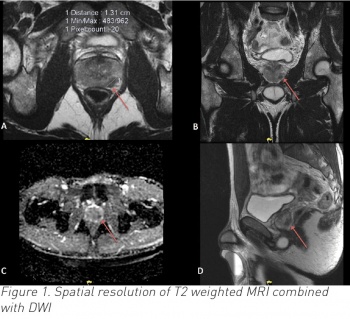

Multiparametic (MP)-MRI prostate is defined as including three of the following four sequences: Standard T1 and T2 cross-sectional imaging, dynamic contrasted enhanced (DCE), diffusion weighted imaging (DWI) and proton spectroscopic MRI (usually omitted). Some centres offer prostate MRI but do not perform MP-MRI and this is not recommended.

The phenomenal spatial resolution of T2-weighted MRI combined with DWI is highly predictive (>90%) for the detection of significant (≥ Gleason grade 7) prostate cancer (see Figure 1). Ideally, it would be used in all patients with an elevated PSA or perhaps as a screening tool in itself, prior to requiring biopsy.

(click to enlarge)

After biopsy, MRI cannot be performed for at least six weeks due to haemorrhage and this can be a difficult time for patients who want treatment quickly. It is currently used in :

• Local staging of recently diagnosed prostate cancer

• Prostate evaluation prior to biopsy so that biopsies can be targeted

• Prostate evaluation after a negative biopsy where suspicion remains (eg. persistently elevated PSA)

• Examining for local recurrence after primary treatment.

• This investigation could potentially replace PSA as a screening tool in the future for prostate cancer (trials ongoing).